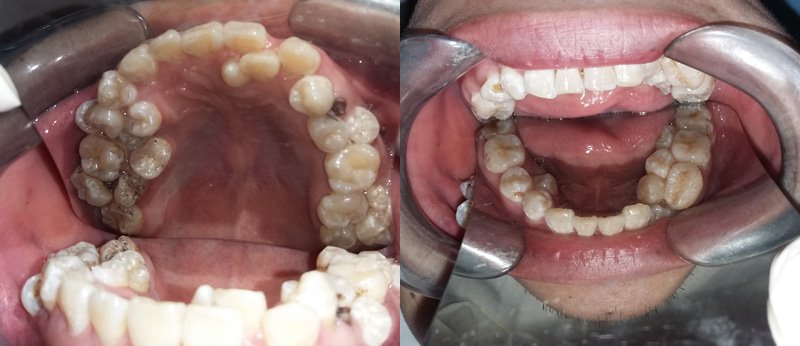

Chỉ đi khám vì răng bị đau, anh Sơn đã làm cho các bác sĩ đều hoảng hốt khi xem hàm răng của anh.

Đây là một trường hợp rất hy hữu từ trước đến này. Anh Đỗ Văn Sơn đã làm các bác sĩ hoảng hốt vì anh thừa tới 17 chiếc răng.

Anh Sơn cho biết, từ năm 15 tuổi đến nay, cứ mỗi năm anh lại thấy mọc thêm 1 chiếc răng. Nghĩ là mọc lẫy bình thường, lại không đau đớn nên anh không hề đi khám. Cách đây 10 ngày, thấy răng sâu ở hàm trên đau nhức khó chịu, anh mới đến Bệnh viện Việt Nam – Cu Ba khám.

Hình ảnh chụp phim cho thấy bệnh nhân mọc thừa răng chi chít

Tại đây các bác sĩ đã hết sức bất ngờ khi phát hiện ngoài chiếc răng sâu, bệnh nhân bị mọc thừa đến 13 chiếc răng ở vị trí răng 4 và 5 trên 2 hàm. Các răng mọc lệch, chen chúc, dàn hàng ngang khiến việc vệ sinh khó khăn, gây sâu, viêm tủy.

BS Nguyễn Thanh Thái, Trưởng khoa Phẫu thuật Tạo hình Hàm mặt cho biết, sau khi chỉ định chụp CT, các bác sĩ lại tiếp tục phát hiện thêm bệnh nhân có 4 mầm răng chưa mọc. Hiện bệnh nhân đã được điều trị tủy dứt cơn đau răng, đồng thời làm xét nghiệm để chuẩn bị mổ bỏ các răng thừa vào tuần tới.

Theo BS Thái, trường hợp thừa nhiều rằng nhất đã từng gặp là 8 chiếc, riêng trường hợp anh Sơn thừa đến 17 chiếc răng thì chưa gặp bao giờ. Qua trường hợp trên, BS Thái khuyến cáo, người dân nên có thói quen khám răng định kỳ 6 tháng 1 lần. Khi thấy răng mọc 2-3 cái một chỗ cần đi khám ngay để can thiệp kịp thời.